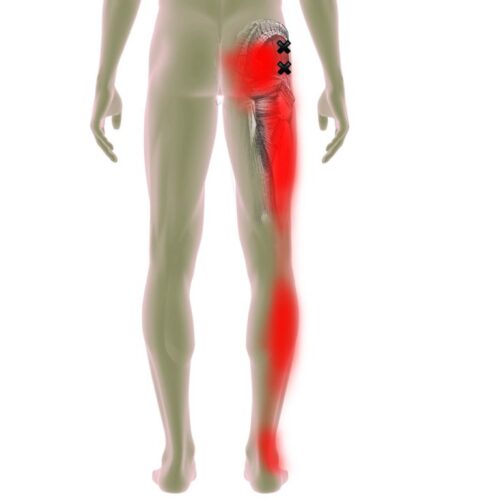

Mυοπεριτονιακός πόνος

Ο μυοπεριτονιακός πόνος αν και είναι η πιο συχνή αίτια μυοσκελετικού πόνου, είναι ο πιο παραγνωρισμένος τύπος πόνου. Αυτό έχει ως αποτέλεσμα έναν μεγάλο αριθμό επισκέψεων σε γιατρούς, χαμένες ημέρες από την εργασία…